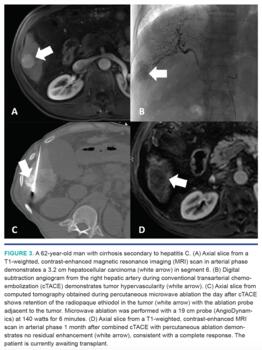

cTACE involves mixing ethidiozed oil with a chemotherapeutic agent, creating a radiopaque emulsion. After this emulsion is delivered, embolization is performed with either a gelatin foam slurry or beads. The radiopaque ethiodol is cleared by normal hepatocytes but retained by the HCC, helping the emulsion preferentially target cancerous cells. Moreover, the emulsion improves the concentrations of the chemotherapeutic agent within the target tissue (Figure 2).41 Finally, its radiopaque nature makes it an excellent target for computed-tomography guided PA (Figure 3) or SBRT (Figure 4). If PA is technically feasible for an HCC measuring 3-5 cm in size, our typical practice is to perform cTACE followed by PA, as the combination of these therapies improves oncologic outcomes.36 PA is most commonly performed either on the same day or the day following cTACE. If PA is not technically feasible or tumor size exceeds 5 cm, the radiopaque ethiodol can be used to localize the tumor for SBRT. Our institutional results demonstrated improvements in both local recurrence and overall survival in patients with unresectable HCC measuring ≥3 cm treated with TACE and SBRT versus those treated with TACE alone.42 We reserve TARE for patients with main-branch portal vein thrombus, radiation segmentectomy, and radiation lobectomy prior to surgical resection.32,33 In our practice, we primarily use glass-based spheres (TheraSphere; Boston Scientific) in patients with HCC.